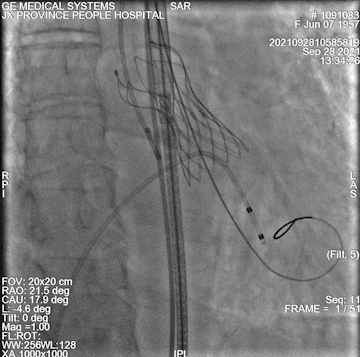

术中操作

加硬导丝输送大鞘

球囊扩张

瓣膜定位

释放后

后扩

球扩后左冠开口到左冠瓣距离

最终造影

术中情况:术中超声及造影评估,左冠灌注未受影响,瓣膜释放后无明显下滑,洪浪院长术中使用VitaFlow Liberty™进行操作,并精准释放,超声及时辅助评估,VitaFlow二代可回收功能给术者增加信心,可以更放心、大胆的挑战高风险病例。